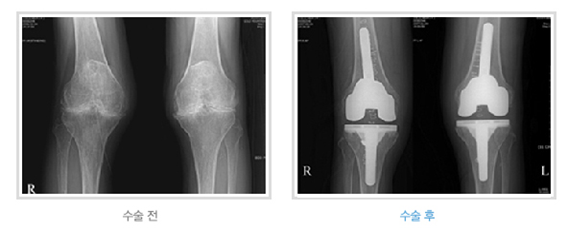

인공관절 수술은 수혈이 필요하고 수술시간도 긴 편입니다. 최근에는 이러한 위험요인을 최소화함으로써 보다 안전하게 수술하기 위해 최소침습수술기법이 발달하고 있습니다. 이러한 추세에 발맞추어 한도병원에서도 최소절개술을 도입, 시행하고 있습니다. 절개부위가 16~20cm에 달했던 기존의 인공관절 수술에 비해 한도병원 인공관절 수술은 절개부위가 10~12cm에 불과해 출혈량이 훨씬 적고 회복이 빠르다는 장점이 있습니다.